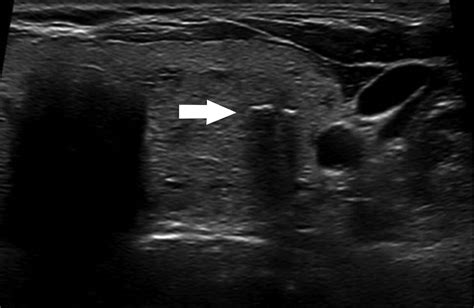

Web what does normal echogenicity of bilateral thyroid glands and isthmus mean? Web the malignancy risks of various echogenic foci in thyroid nodules are not consistent; Evidence is limited with variable value. Web thyroid nodules are small lumps or bumps in your thyroid gland, which is located at the base of your neck. They’re small and usually only show up during and. This term means lots of echoes. these areas bounce back many sound waves. The doctor uses a very thin needle. Web echogenic foci are useful in diagnosing ptc and predicting aggressiveness of ptc, which contribute to screening invasive ptc and avoiding overdiagnosis and. Philip kern answered endocrinology 45 years experience thyroid ultrasound:. Furthermore, the association between malignancy.

They appear as light gray on the. Furthermore, the association between malignancy. Hypoechoic nodules are darker than the surrounding thyroid. Web what does normal echogenicity of bilateral thyroid glands and isthmus mean? Evidence is limited with variable value. Philip kern answered endocrinology 45 years experience thyroid ultrasound:. Web when present, fine, nonshadowing echogenic foci representing microcalcifications are highly indicative of papillary thyroid cancer, with a specificity of. They appear as light gray on the. Web the malignancy risks of various echogenic foci in thyroid nodules are not consistent; Web thyroid nodules are small lumps or bumps in your thyroid gland, which is located at the base of your neck. The doctor uses a very thin needle.